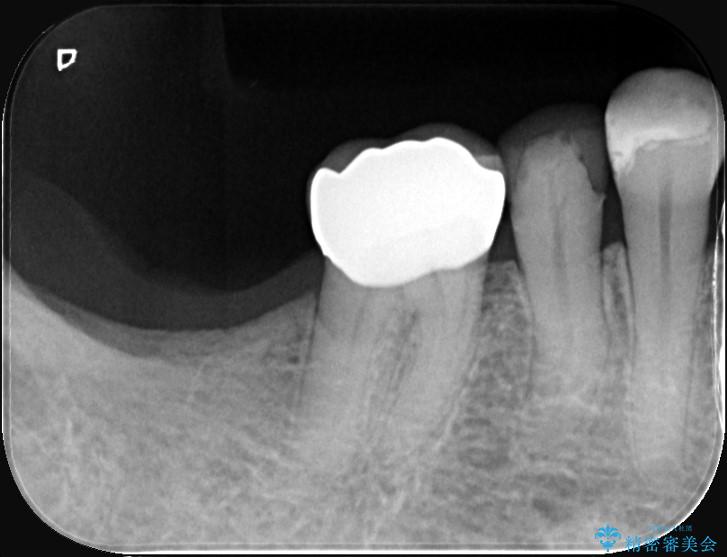

他院で装着されたセラミックインレー(MOD窩洞)が破折したとご来院されました。

MOD窩洞のように欠損範囲が大きい場合、インレーでは咬合力に対する耐久性が不足し、破折リスクが高くなるケースがあります。

歯の中央から両側にかけて大きく削られている(MOD窩洞)状態でした。

噛む力がかかることで、インレーでは負担に耐えきれず破折してしまったと考えられます。